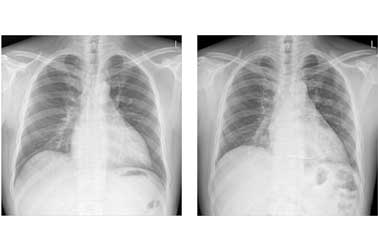

사례(1)

심방중격결손을 교정 받지 않은채 살아온 54세 환자의 흉부 엑스선 사진

장기간의 좌 - 우 단락으로 인하여 폐동맥 고혈압이 심하게 진행하였고, 심장의 크기도 보통에 비하여 심하게 늘어나 있습니다.